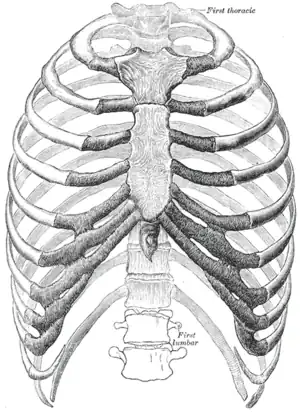

![]() The human rib cage (Source: Gray's Anatomy of the Human Body, 20th ed. 1918) | |

Rib cage

The first seven sets of ribs, known as "true ribs", are attached to the sternum by the costal cartilages. The first rib is unique and easier to distinguish than other ribs. It is a short, flat, C-shaped bone, and attaches to the manubrium.[6] The vertebral attachment can be found just below the neck at the first thoracic vertebra, and the majority of this bone can be found above the level of the clavicle. Ribs 2 through 7 then become longer and less curved as they progress downwards.[7] The following five sets are known as "false ribs", three of these sharing a common cartilaginous connection to the sternum, while the last two (eleventh and twelfth ribs) are termed floating ribs.[2] They are attached to the vertebrae only, and not to the sternum or cartilage coming off of the sternum.

In general, human ribs increase in length from ribs 1 through 7 and decrease in length again through rib 12. Along with this change in size, the ribs become progressively oblique (slanted) from ribs 1 through 9, then less slanted through rib 12.[7]

The rib cage is separated from the lower abdomen by the thoracic diaphragm which controls breathing. When the diaphragm contracts, the thoracic cavity is expanded, reducing intra-thoracic pressure and drawing air into the lungs. This happens through one of two actions (or a mix of the two): when the lower ribs the diaphragm connects to are stabilized by muscles and the central tendon is mobile, when the muscle contracts the central tendon is drawn down, compressing the cavity underneath and expanding the thoracic cavity downward. When the central tendon is stabilized and the lower ribs are mobile, a contraction of the diaphragm elevates the ribs, which works in conjunction with other muscles to expand the thoracic indent upward.